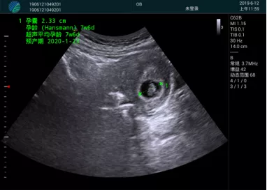

病例一:

清晰顯示孕囊,通過軟件包計(jì)算孕齡7w+6d

M20實(shí)時(shí)引導(dǎo),術(shù)中清晰顯示孕囊被破壞和抽吸針的過程,清晰顯示吸引針

抽吸結(jié)束后縱切子宮,孕囊已被完全抽吸,未見明顯殘留